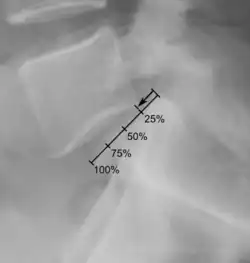

Степень соскальзывания

Боковая рентгенограмма покажет степень смещения позвонка к нижележащему:

- Степень I — смещение до 25 %.

- Степень II — смещение от 26 % до 50 %.

- Степень III — смещение от 51 % до 75 %.

- Степень IV — смещение от 76 % до 100 %.

- Степень V развивается, когда позвонок полностью отделяется от соседнего позвонка (спондилоптоз).